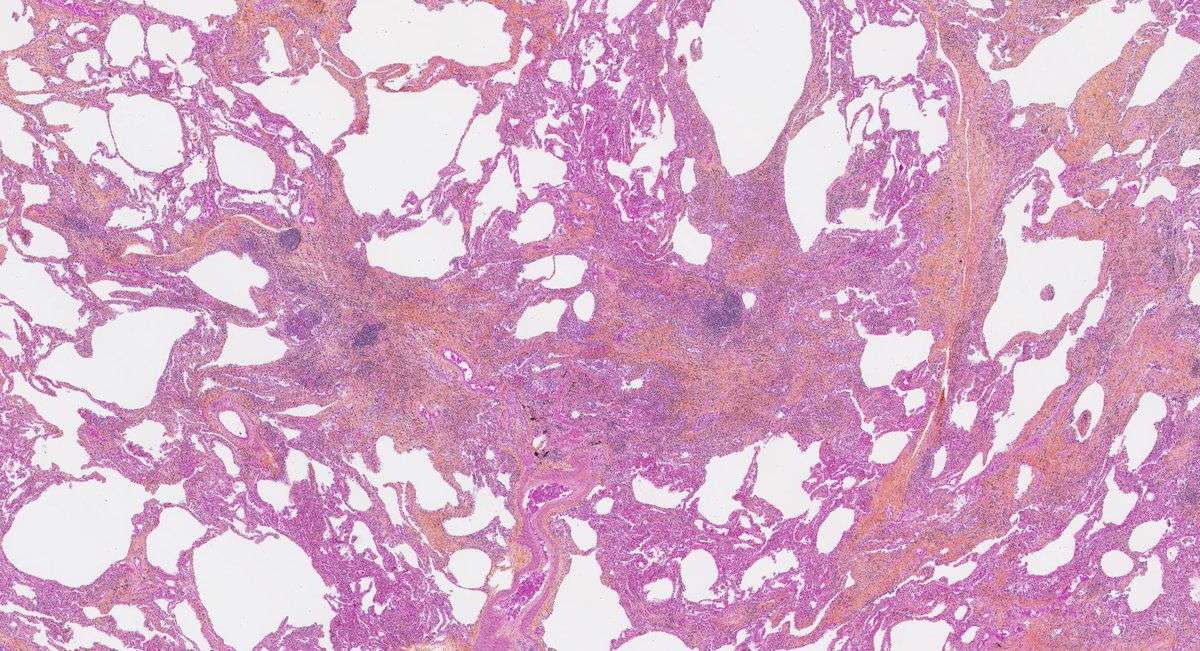

Usual Interstitial Pneumonia shows peripheral, lower predominant fibrosis in the #grosspath by @_Romo_Navarro Microscopically you can appreciate patchy fibrosis, fibroblastic foci & honeycomb #pulmpath #explantsRawesome #transplantpath #ILD